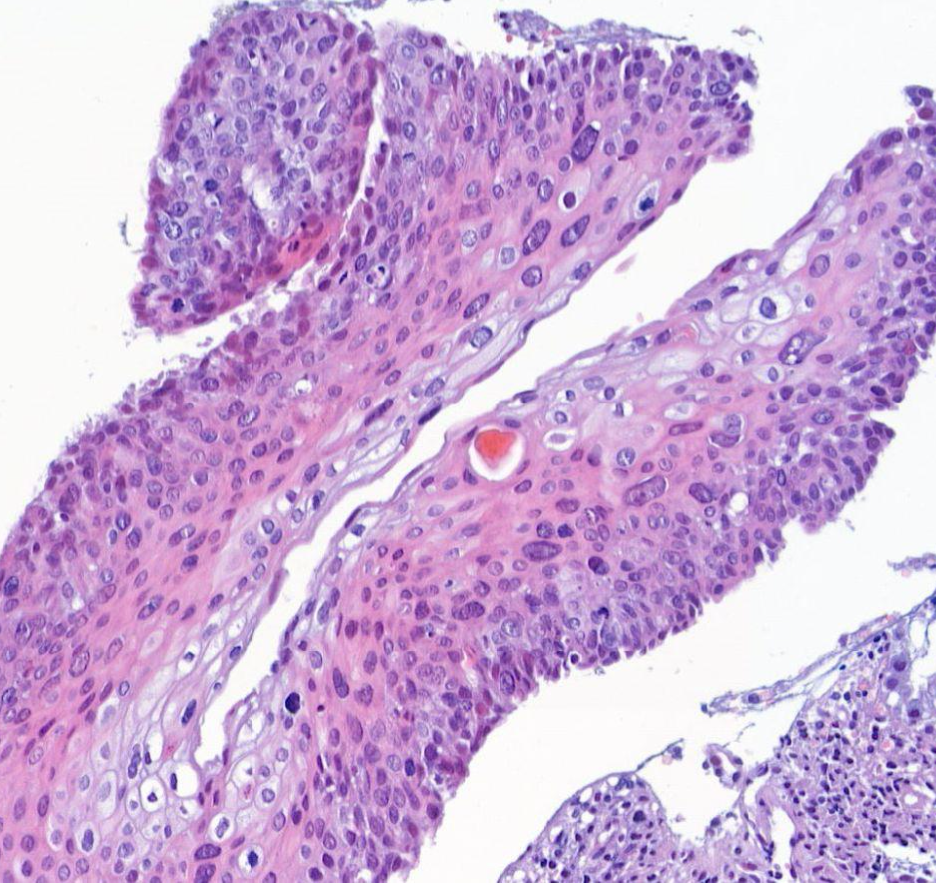

Diagnose?

Squamöse intraepitheliale Läsion (SIL)

Zervikale intraepitheliale Neoplasie (CIN)

Plattenepithelkarzinom der Zervix